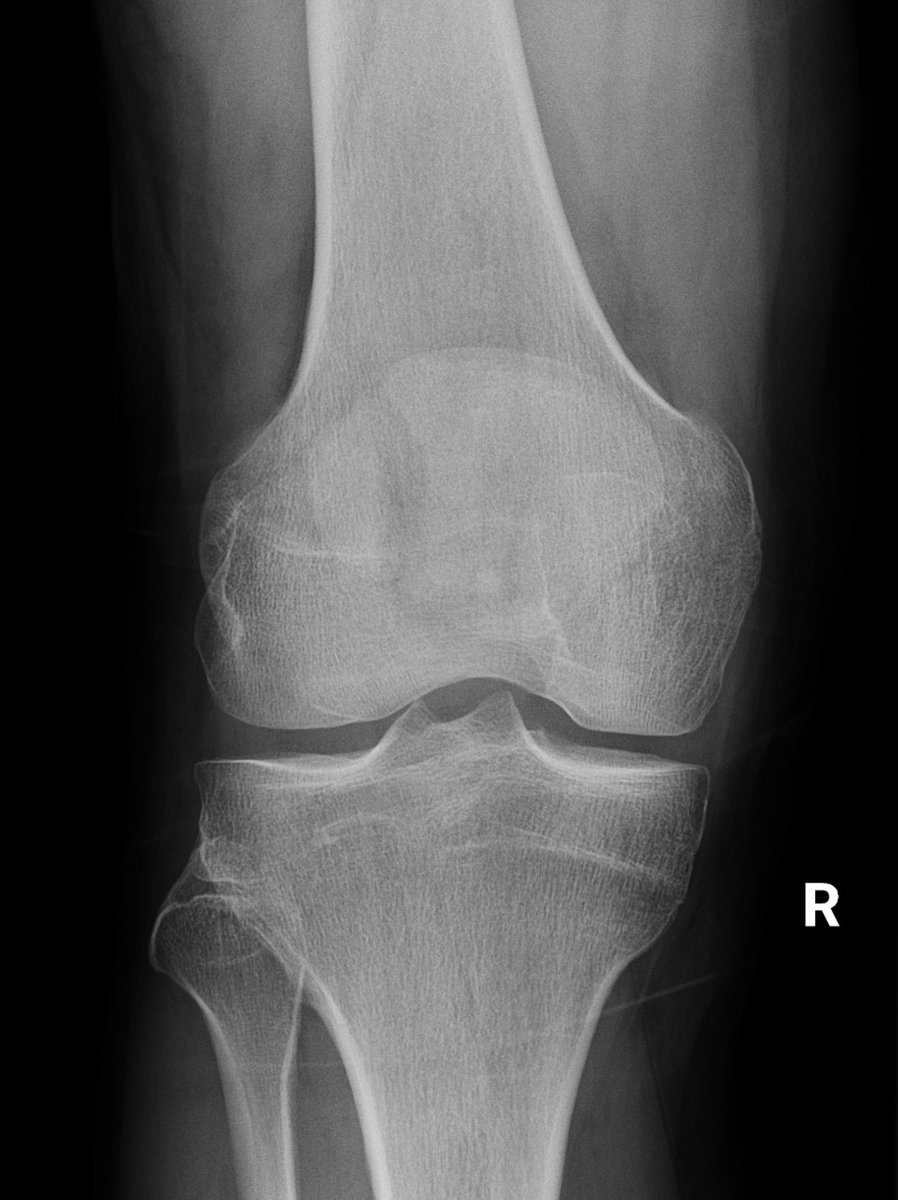

Interesting case. Calcific tendonitis in distal quadriceps. Symptomatic, treatment options? @KneeUnit @kneedoclond @kashakhtar @expertknee

@DrJN_SportsMed @kashakhtar @expertknee @KneeUnit @kneedoclond Yes, not seen one this amount of calcification before - admittedly I don’t use ultrasound, but I do see a lot of knee x-rays

@kashakhtar @expertknee @DeepuSethi @KneeUnit @kneedoclond Agree these are quite big deposits though…

@kashakhtar @expertknee @KneeUnit @kneedoclond @DrJN_SportsMed Thinking this is quite a big lesion and very well calcified. Speaking to shoulder surgeons, they use shockwave and needling, but for much smaller lesions.